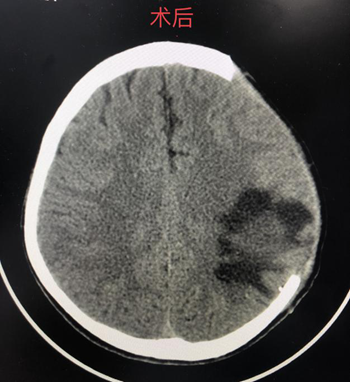

(术前脑部CT)                       (术后脑部CT)

术后患者病情突然变化,出现昏迷,双侧瞳孔散大......廖驭国主任凭着多年的经验判断患者出现了“正常灌注压突破综合征”(该病为脑动静脉畸形栓塞术后最为危重的并发症),有急诊开颅手术指征,最后由神经外科周康胜副主任成功为患者实施显微镜下血肿清除+去骨瓣减压+硬脑膜修补术,术后患者神志好转,双侧瞳孔缩小至正常,术后2天,患者神志完全清醒,停用呼吸机及拔除气管插管,经过后续治疗,患者能简单言语及对答,右侧肢体肌力基本恢复,能下地缓慢行走,已康复出院。